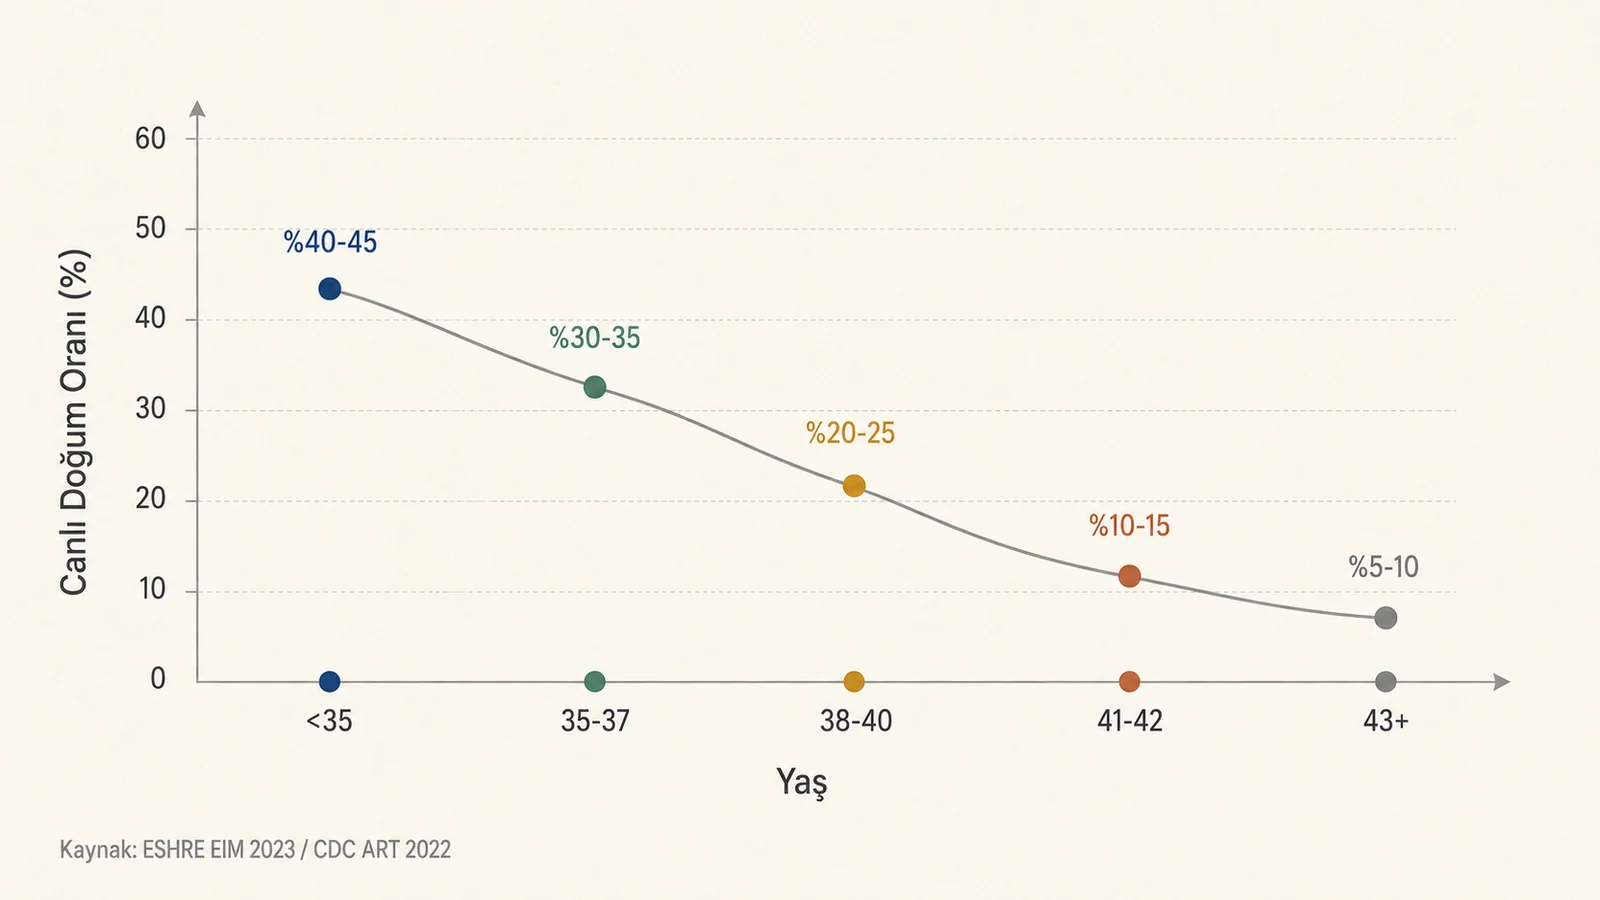

Yumurta dondurma nedir, kimler için uygundur, yaşa göre başarı neden değişir ve kaç yumurta hedeflenebilir? Oosit kriyoprezervasyonu için kanıt temelli rehber.

Yaşa göre tüp bebek başarısı nasıl değişir? 30'lu yaşlar, 35 sonrası düşüş, 40 yaş ve üzeri için embriyo kalitesi, rezerv, transfer stratejisi ve gerçekçi beklenti rehberi.

Yumurta dondurma nedir, kimler için uygundur, yaşa göre başarı neden değişir ve kaç yumurta hedeflenebilir? Oosit kriyoprezervasyonu için kanıt temelli rehber.

Tüp bebekte kaç yumurta yeterli kabul edilir? Yaş, AMH, olgun yumurta, embriyo kaybı, PGT-A, OHSS riski ve düşük rezerv için gerçekçi karar rehberi.